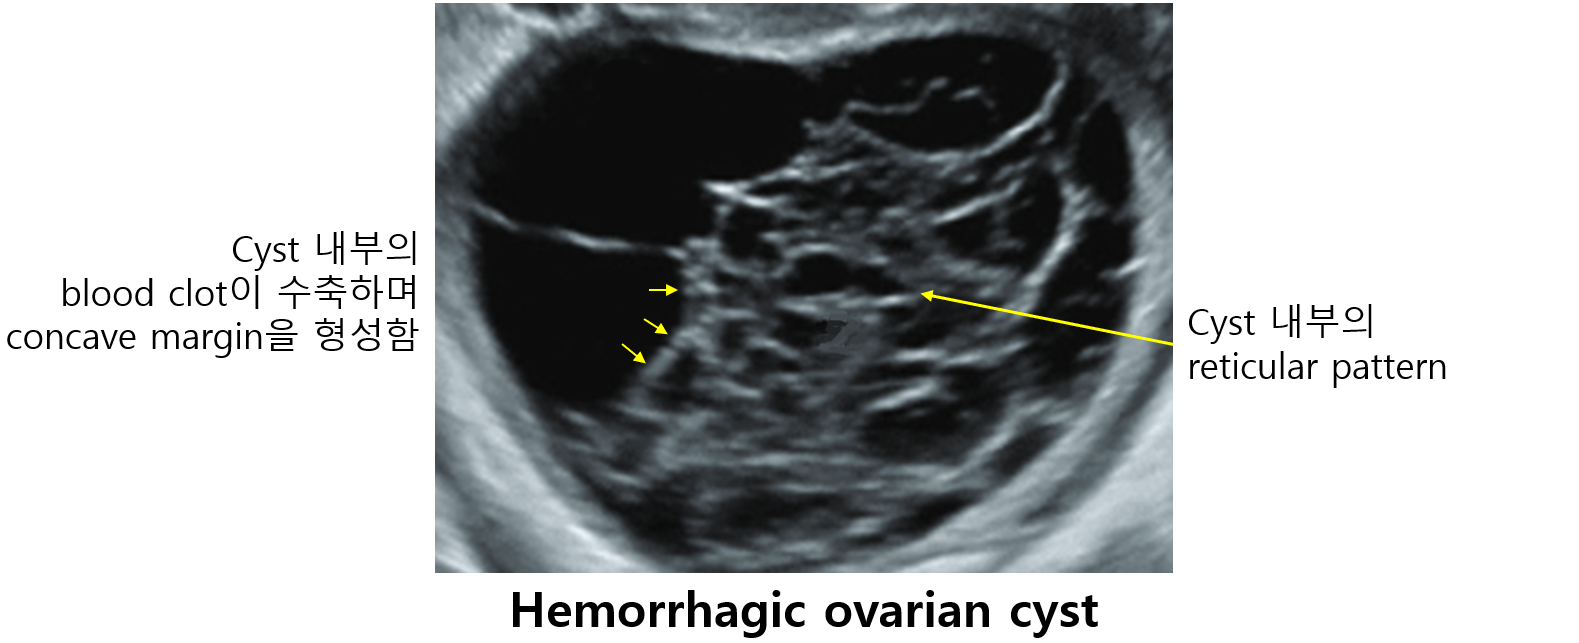

(1) US: Reticular pattern, ruptured cyst wall, with nearby fluid collection